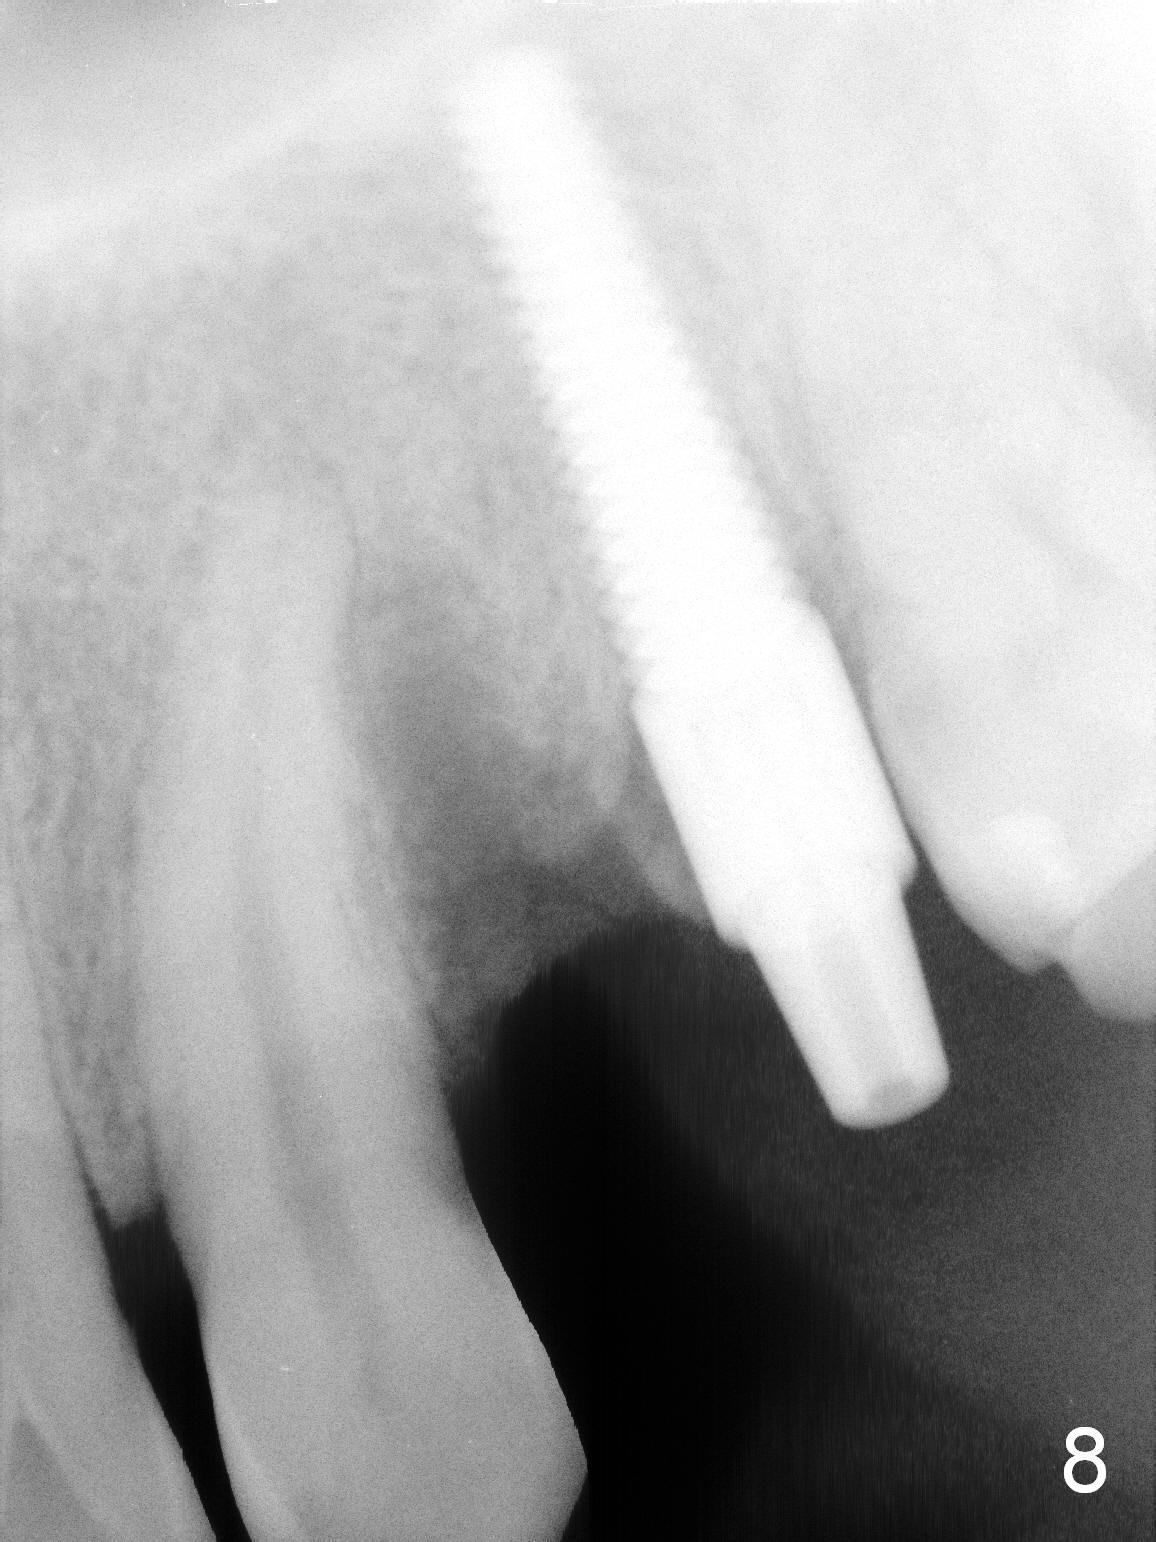

Taking 2 additional PAs with sensor 1 is frustrating (Fig.1,2), no apices shown.  Osteotomy is done smoothly with 2 mm pilot drill at 20 mm, 2.5 mm reamer at 17 mm, and 3 mm reamer at 14 mm and 4.5x20 mm tap at 17 mm.  The 1st intraop PA is taken with sensor 1 when 2 of 4.5x20 mm implants are placed (Fig.3); the implant at #12 is close to the root of the tooth #11.  The 2nd PA is taken with sensor 2: the apex of #11 touches the implant at #12 (Fig.4).  There is no separation when panoramic X-ray is taken (Fig.5).  Effort is exerted to re-direct the osteotomy twice (Fig.6: tap; Fig.7: implant) without success.  When the implant is removed, a PA is taken; it appears that the root of the tooth #11 has no damage (Fig.8).  To obtain the best recovery, socket preservation is carried out with 50/50 cortical/cancellous allograft mixed with Osteogen (Fig.12 *) and Collagen Dressing (Fig.9: #12).  A 2 (or 3)-unit provisional bridge (Fig.10: #12,13) is fabricated over the implant (Fig.9 I)/abutment (A) to cover these 2 sockets.  After acid etching #11 D surface (Fig.9 >) and relining (Fig.11 *), the provisional bridge is bonded to the tooth #11 (Fig.11,12 black >) so that bone graft will be less likely dislodged.